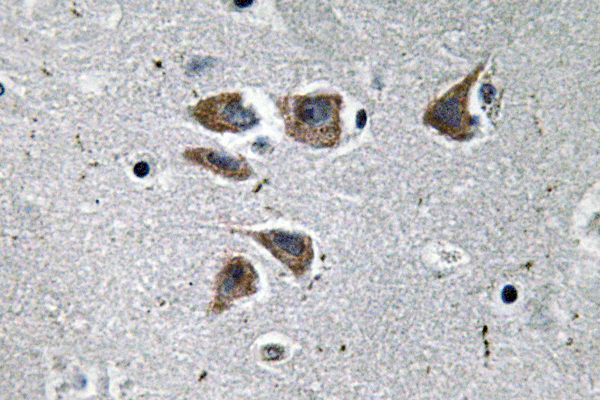

Anti-NPY AntibodyA98310

ApplicationsELISA, ImmunoHistoChemistry

ReactivityHuman, Mouse, Rat

- SizePrice